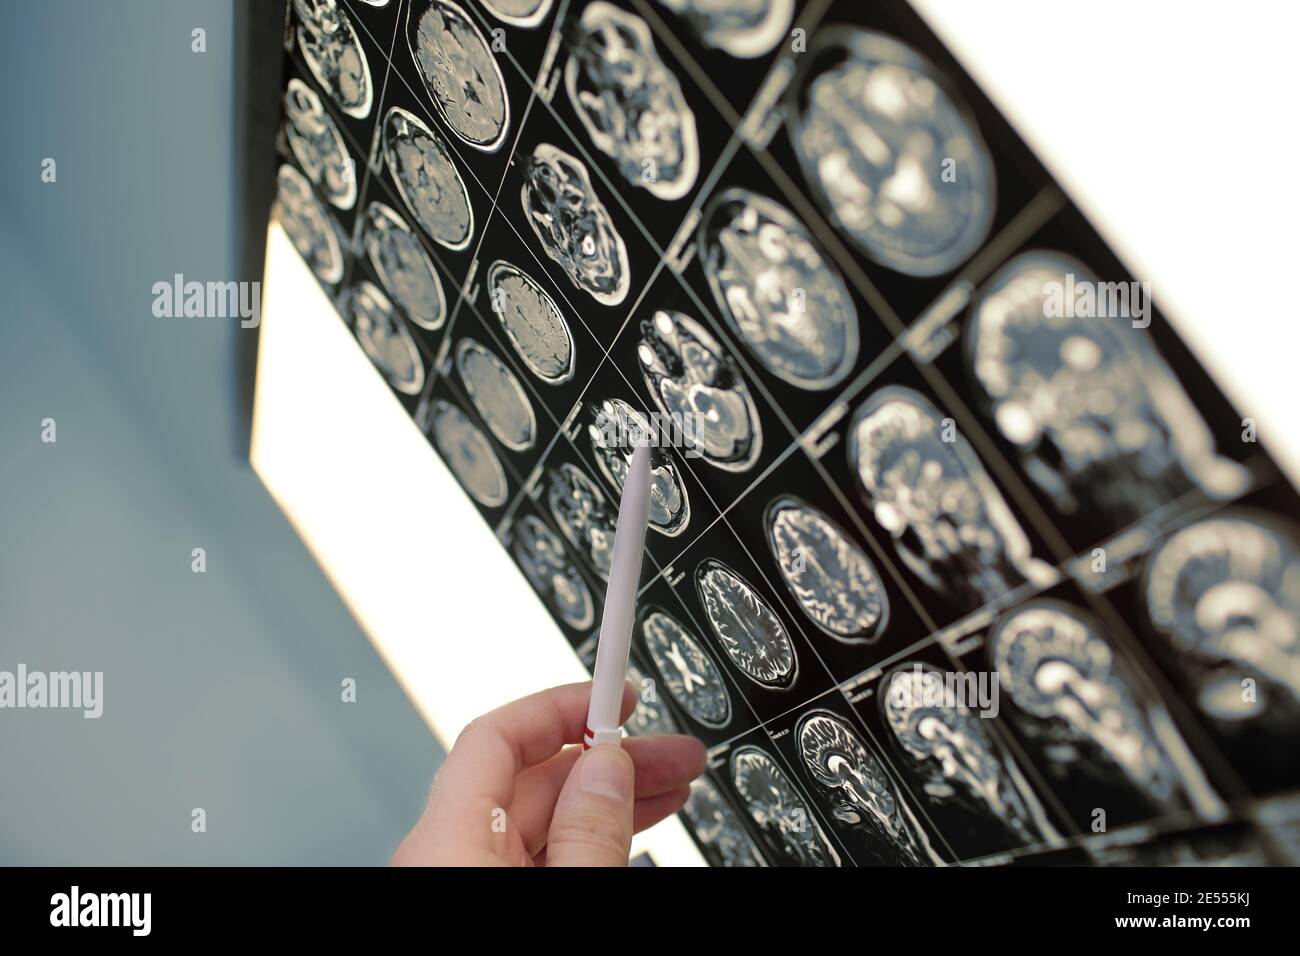

Le médecin montre avec un stylo sur la lésion cérébrale. Banque D'Imageshttps://www.alamyimages.fr/image-license-details/?v=1https://www.alamyimages.fr/le-medecin-montre-avec-un-stylo-sur-la-lesion-cerebrale-image399025974.html

Le médecin montre avec un stylo sur la lésion cérébrale. Banque D'Imageshttps://www.alamyimages.fr/image-license-details/?v=1https://www.alamyimages.fr/le-medecin-montre-avec-un-stylo-sur-la-lesion-cerebrale-image399025974.htmlRF2E555KJ–Le médecin montre avec un stylo sur la lésion cérébrale.